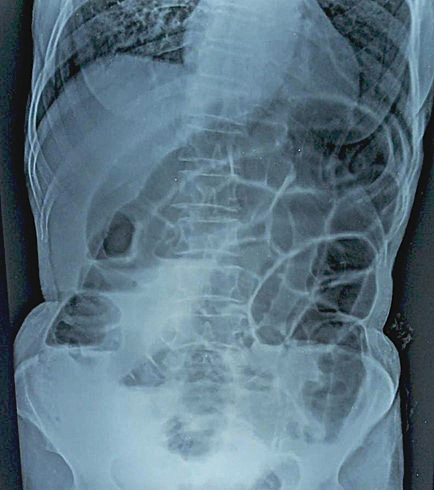

Routine laboratory investigations were unremarkable except for ABG which was suggestive of metabolic acidosis. Erect Abdominal X-ray showed multiple air-fluid levels with dilated bowel loops and absence of rectal gas shadow, indicative of mechanical obstruction (Figure 1).

Figure 1. Erect Abdominal X-ray showed multiple air-fluid levels with dilated bowel loops